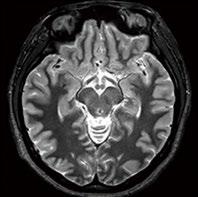

Fig 1: Next generation MRI is being used to gather data on brain tissue volumes Dr. Steve McNally

From this season at Manchester United Football Club, we have started to gather data by using MRI (see fig 1) to measure volumes of brain tissue in specific areas, to monitor for a decrease in volumes over time. If the volumes become unusual or deviate from the norms that we would expect, it may help us identify early changes of CTE that need closer monitoring. This is a new, long-term data gathering study in our cohort of players that has been facilitated with the new next generation MRI3 now in place at our medical centre.